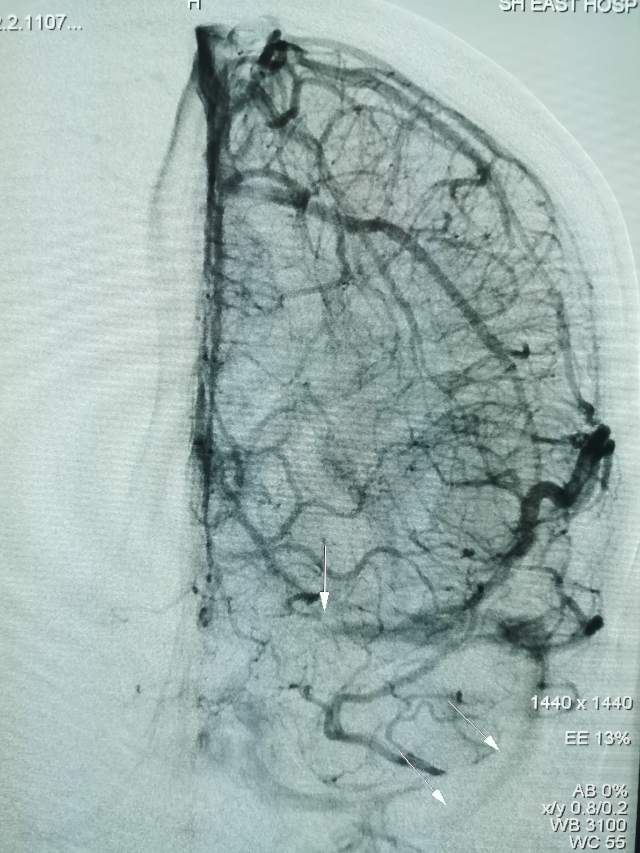

44岁盐城帅哥,因“头痛3天”发现静脉窦血栓合并“颅内动脉瘤“来诊。颅内动脉瘤之一是瘤体累及眼动脉的相对宽颈微小动脉瘤(2.5mm),此部位动脉瘤存在破裂出血的风险,而且静脉窦血栓的治疗也会加重此风险,有必要同步先消除这个潜在的风险。病变累及眼动脉,如果治疗过程中受到累及存在失明风险,需要重点保护。最终,采用一个支架一个圈的“简约模式:花费少,效果好”结束手术,眼动脉保留良好。